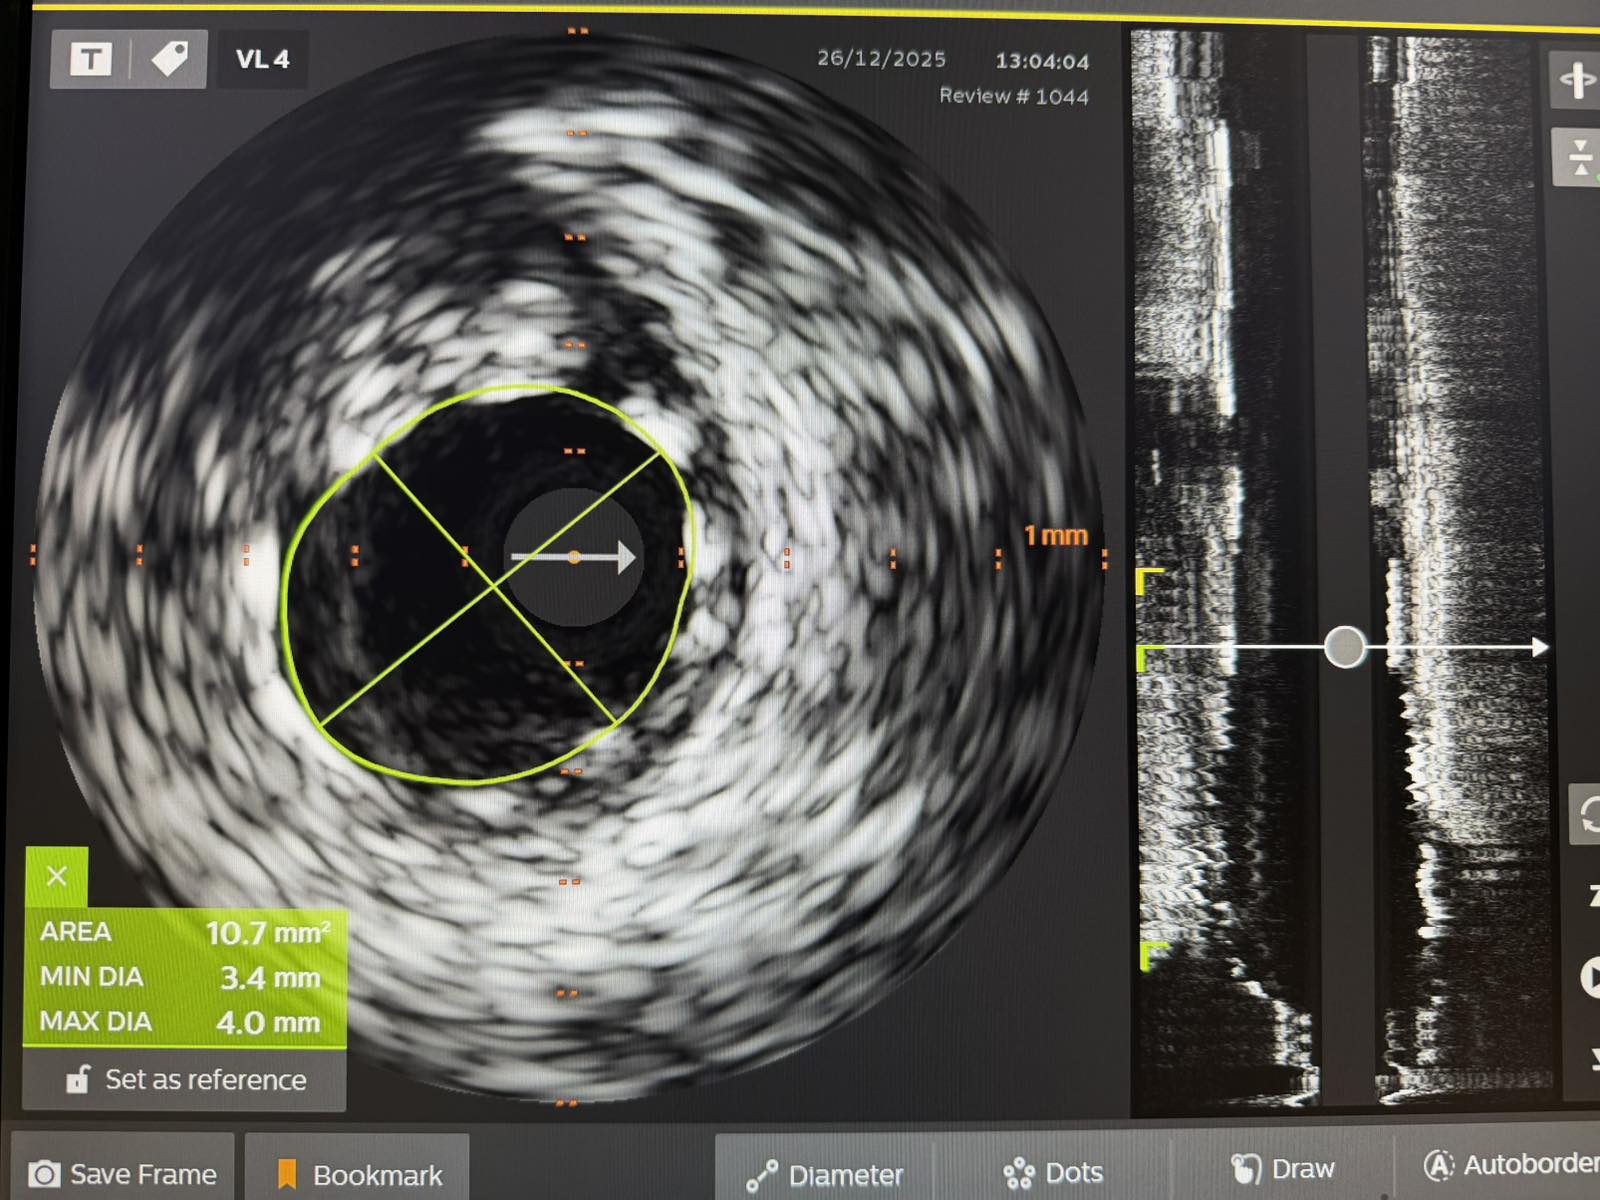

„Pacijent je imao simptome angine pectoris. Nakon urađene koronarografije verifikovana je teška trosudovna koronarna bolest, gdje su bolesne bile desna koronarna arterija, dok je na lijevoj strani kritično mjesto bilo na glavnom stablu  odakle ide račvanje u dvije grane. Takvi pacijenti uglavnom završavaju na kardiohirurškom konzilijumu i na operaciji bajpasevima. Međutim, odluka konzilijuma u Banjaluci je bila da se, zbog godina života pacijenta,  radi perkutana intervencija na desnoj i lijevoj koronarnoj arteriji uključujući glavno stablo.Takve procedure zahtijevaju da se rade sa kontrolom imidžinga, savremene intravaskularne dijagnostike (IVUS), što smo mi i uradili. To dodatno povećava bezbijednost i preciznost zahvata. Procedura je trajala svega 45 minuta, a pacijent je već narednog dana otpušten kući“, izjavio je dr Janjičić.